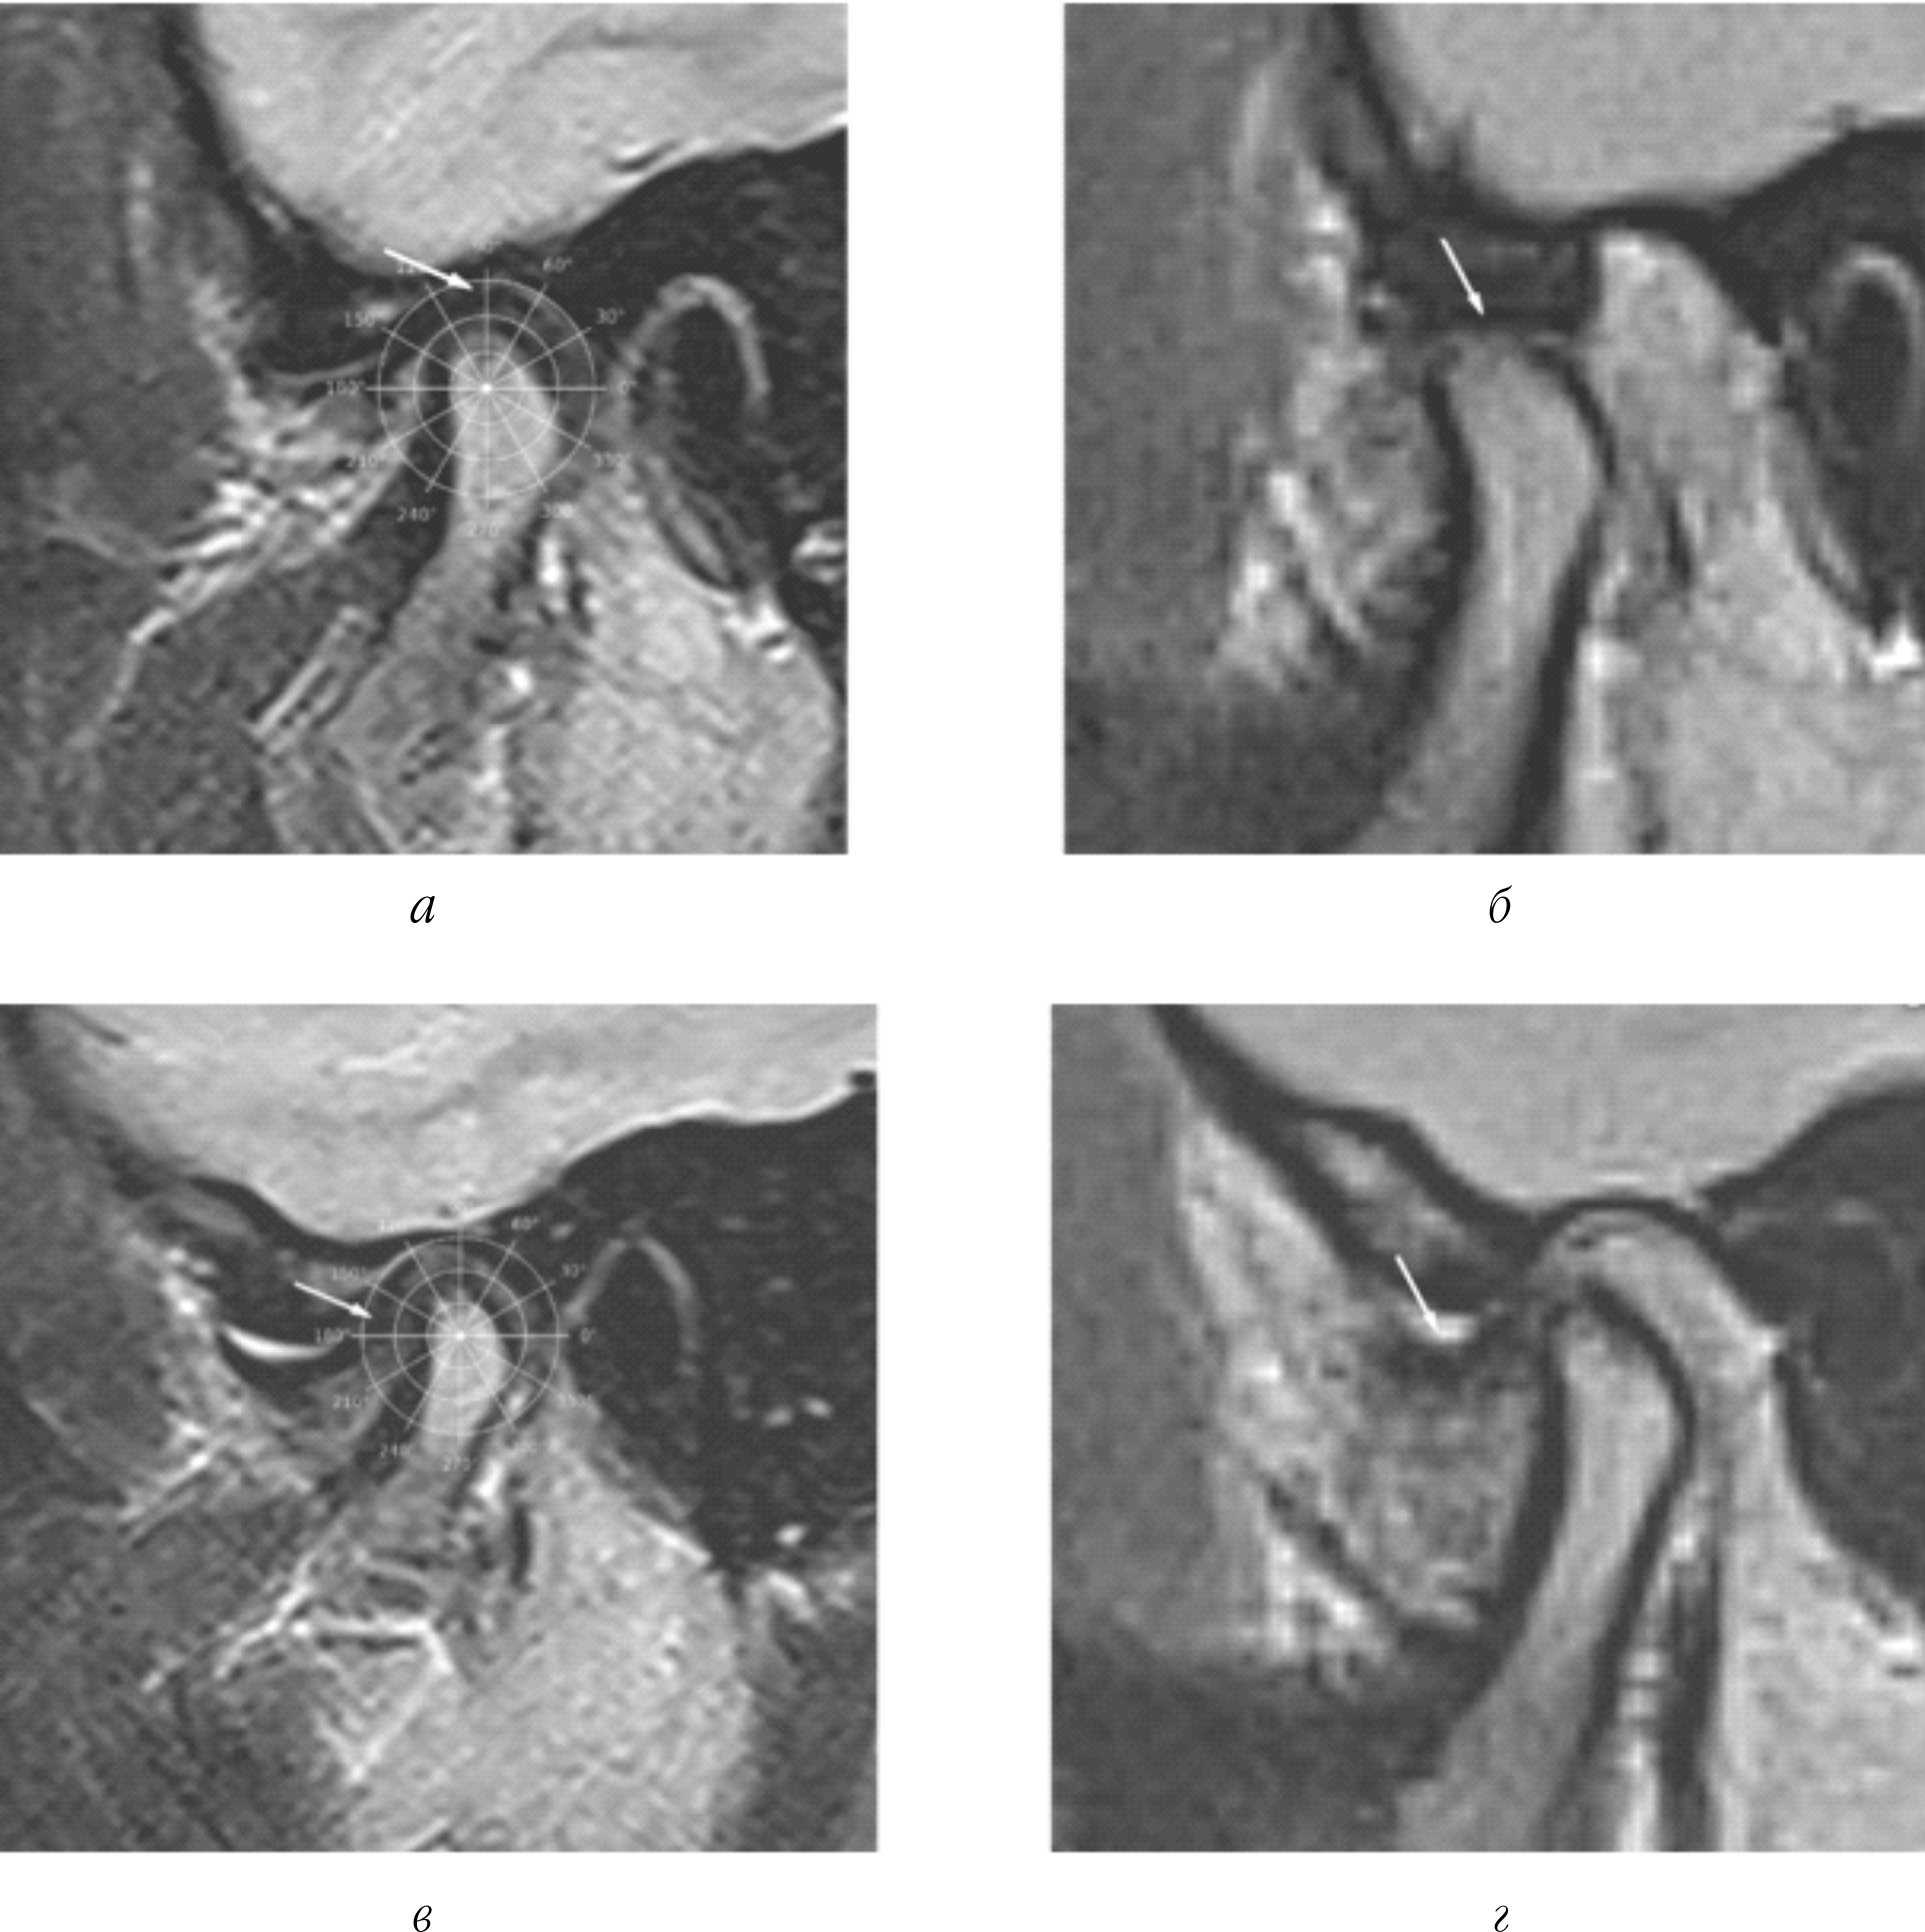

Рис. 1. Угловые значения показателя дислокации заднего полюса диска по отношению к верхнему полюсу ГНЧ в полярной системе координат в диапазоне положения заднего полюса диска от 90° до 180°: a – угловое значение 90°; б – угловое значение 120°–2°; в – угловое значение 150°–15°; г – угловое значение 180°

Показатели углового значения дислокации заднего полюса суставного диска по отношению к верхнему полюсу ГНЧ, интерпретируемые в цифровом виде (рис. 1).

В процессе диагностики определяют угловое значение показателя дислокации заднего полюса диска по отношению к верхнему полюсу ГНЧ в полярной системе координат с расположением ее начала в геометрическом центре мыщелкового отростка нижней челюсти в диапазоне положения заднего полюса диска от 90° до 180° в положении множественного фиссурно-бугоркового контакта зубов, определяют показатель физического состояния каждого суставного диска, принимающий значения: недеформированный и деформированный, выявляют возможность репозиции диска при широком открытии рта, определяя показатель репозиции каждого суставного диска при открывании рта, принимающий значения: полное, частичное, отсутствует, для постановки диагноза используют комплексный критерий состояния ВНЧС, включающий:

1) показатель дислокации заднего полюса каждого суставного диска по отношению к верхнему полюсу суставной головки в полярной системе координат с расположением ее начала в геометрическом центре мыщелкового отростка нижней челюсти в состояниях фиссурно-бугоркового контакта зубов в диапазоне от 90° до 180°;